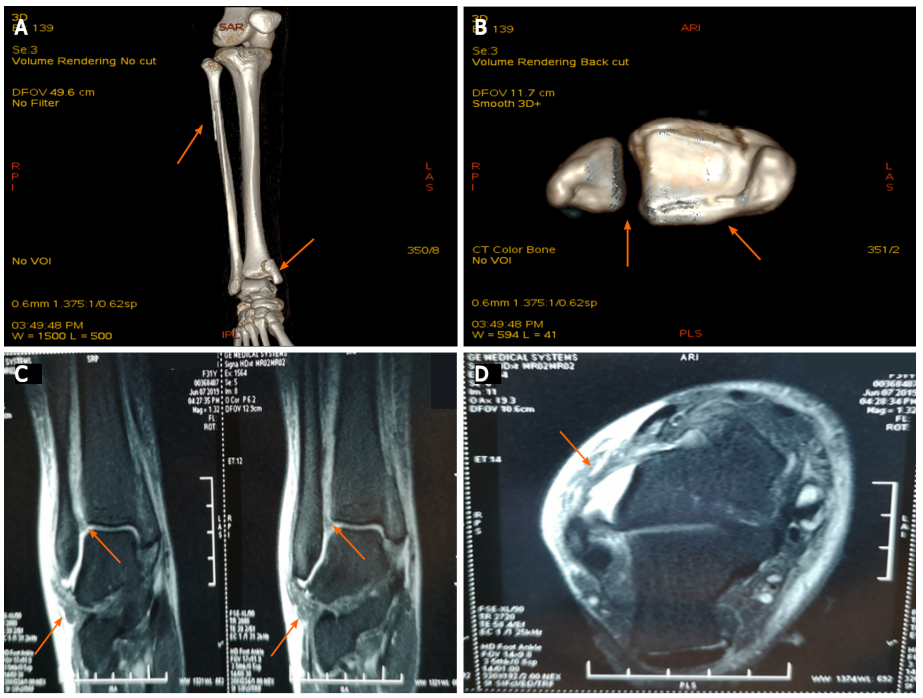

1位31岁女性患者在5天前步行时不小心扭伤了右脚踝。小腿的全长X线片显示腓骨近端骨折,下胫腓关节分离,内踝骨折累及后踝。磁共振成像显示胫腓前下韧带和距腓前韧带断裂。我们诊断出一种罕见的Maisonneuve骨折类型,合并腓骨近端骨折、下胫腓关节分离、内踝骨折以及胫腓前下韧带和距腓前韧带断裂。患者接受切开复位内固定术,术后6个月随访,临床效果良好。(此患者同时具有旋前外旋踝关节骨折和旋后内收踝关节骨折的特点。本例腓骨骨折呈长斜骨折,骨折线靠近腓骨。还有下胫腓分离。这些特征与典型的Maisonneuve骨折相似,后者是一种旋前外旋踝关节骨折。而内踝典型的旋前外旋踝关节骨折通常表现为三角韧带的斜位断裂,而不表现为距腓前韧带或跟腓断裂(11)。本例踝内侧骨折为垂直骨折,距腓骨前韧带断裂,与旋后内收踝关节骨折一致。

图片

图2:A:踝关节和小腿的CT正面图(箭头);B:踝关节CT扫描(箭头);C:踝关节的矢状位MRI(箭头);D:踝关节的横断面MRI(箭头);A和B:CT显示腓骨近端骨折、下胫腓关节分离、内踝骨折累及后踝(箭头);C和D:MRI显示胫腓前下韧带和距腓前韧带断裂(箭头)。